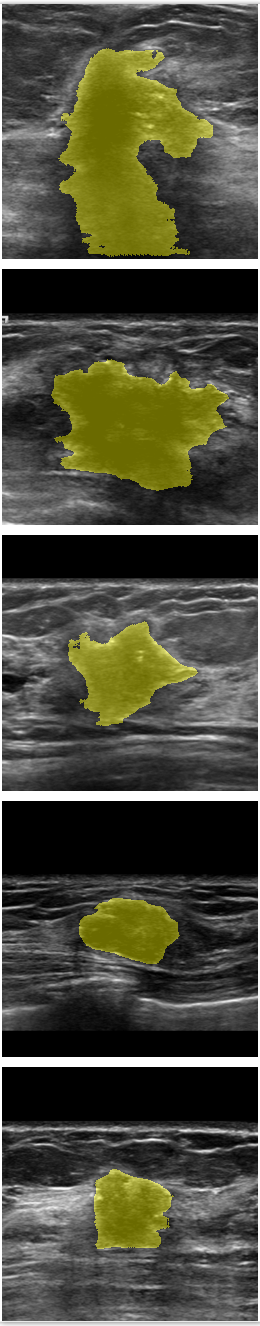

Refer to caption

Figure 7: Comparison of SPCGAN and other segmentation methods of malignant lesions.(a) shows original image of malignant lesions, (b) shows the manual annotation, (c) shows the result of SPCGAN ,(d), (e) and (f) show results from FCN(ResNet), Mask R-CNN and the level set method.

The examples given in Fig.7 correspond to the segmentation results of our SPCGAN, FCN(ResNet), Mask R-CNN and the level set method from malignant lesions. The FCN(ResNet) tends to oversegment the cancer when there is posterior shadowing, especially for the lesion in the first row. SPCGAN shows relatively more robust performance compared to FCN(ResNet), Mask R-CNN and the level set method.